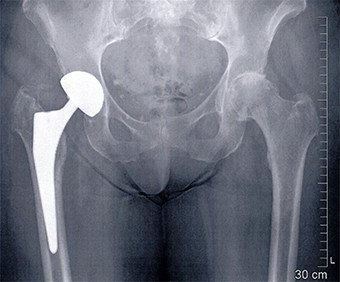

Nach acht Wochen war der Muskel stabil angeheilt und ein künstliches Hüftgelenk wurde implantiert. Die Patientin konnte die Hüfte sofort voll belasten und war nach vier Monaten wieder ohne Stöcke schmerzfrei gehfähig. Dieses operative Verfahren ist zwar aufwendig, ergibt jedoch nach unserer Erfahrung die besten Resultate. Dies beweisen auch die vielen zufriedenen Patienten, welche wir mit dieser Technik operiert haben.